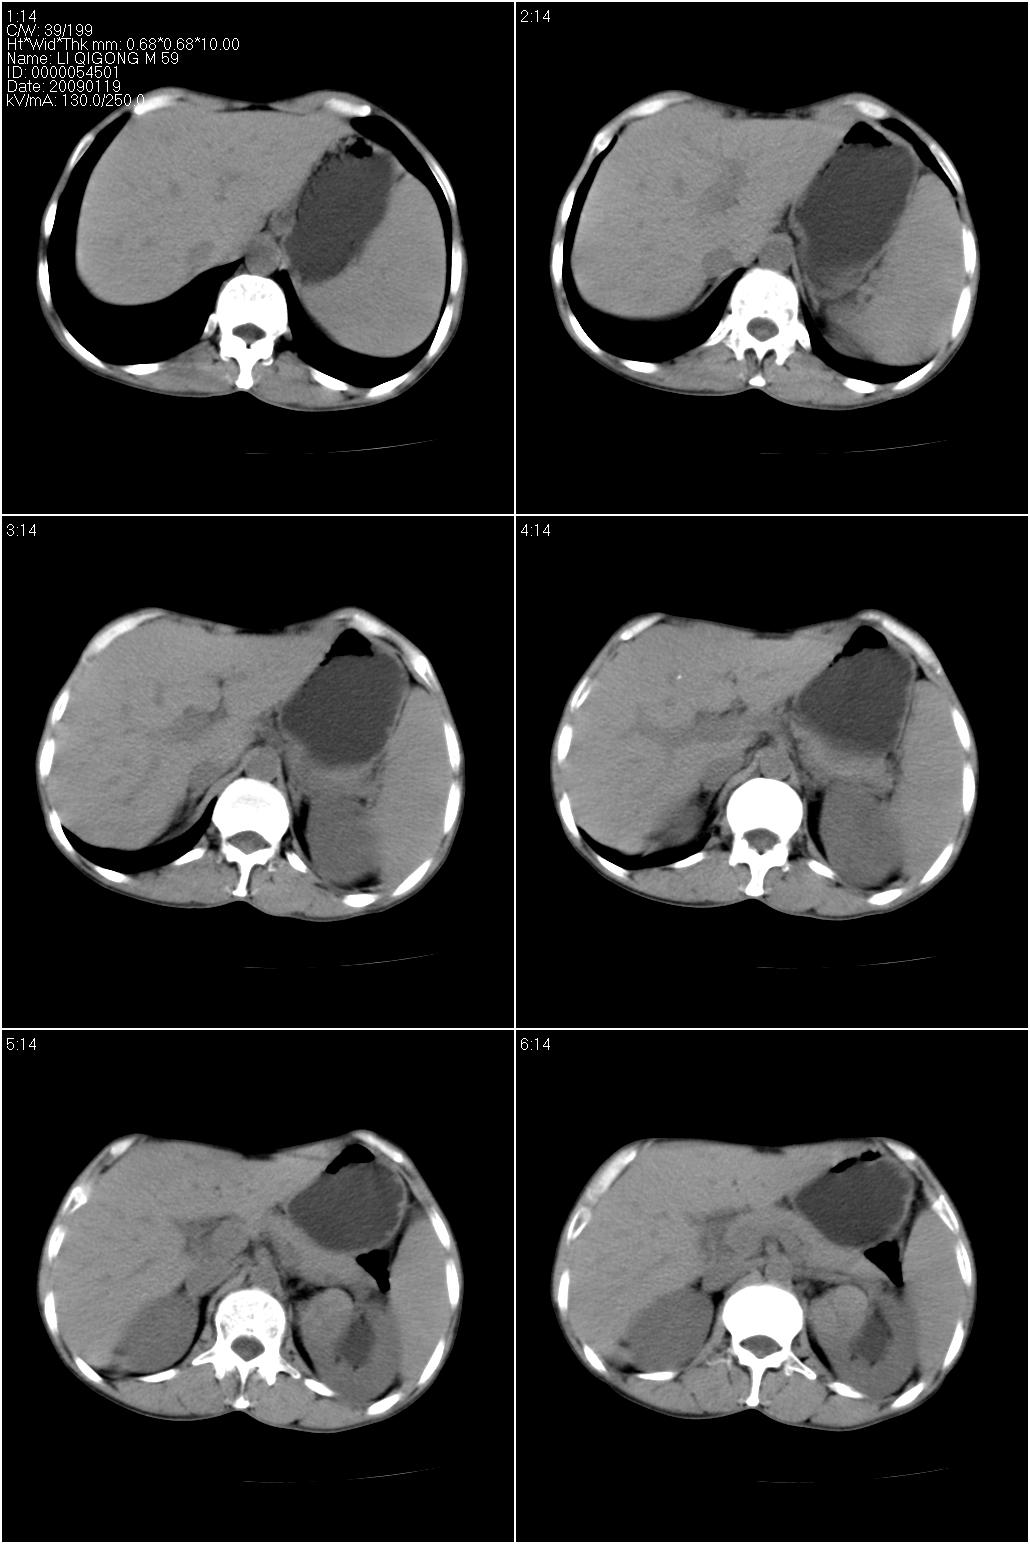

标题: CT17771:男性,59岁。体检发现左肾占位。

男性,59岁。体检发现左肾占位。自诉无尿血、尿痛。

无痛无血尿,左肾实质占位,有明显强化,中心坏死不规则,应该肾癌无疑。

应该考虑左肾癌并肾盂积水

诊断依据:

1、中老年男性.

2、左肾占位,呈不均匀性强化,中央有无强化的坏死区。

3、左肾门旁有侧枝开放,提示左肾静脉癌栓形成可能。

4、患者自诉无血尿,但不一定镜下无血尿。